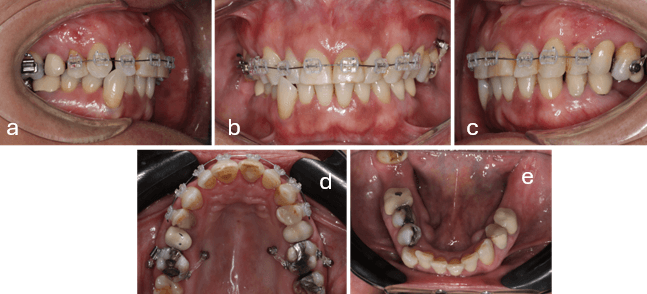

Después de 8 meses de progreso del tratamiento, avanza a arco acero superior 0.017x0.025. (fig. 6d) Se ancla con ligadura metálica desde vestibular y palatino de la pieza 1.6 y 2.6 hacia los mini implantes asegurando las mecánicas de intrusión. En la arcada inferior se utiliza arco 0.016x0.022 Termocooper Orthometric (Marilia, Sao Paolo, Brasil) se regularizan los espacios para la pieza 4.3 y mejorar el apiñamiento anteroinferior con la mecánica de distalización. Se realiza la colocación del implante de 3.6 (fig.6e).

Se retira ortodoncia superior con la redistribución de espacios, posteriormente se colocan carillas provisorias de adaptación (fig.7b). En inferior se mantiene arco acero 0.017x0.025 se realiza doblez de off set para piezas 4.4 y 4.5. Con confección adicional de cantiléver anclado a el implante del 4.6 para mejorar canteo del plano oclusal inferior (fig. 7a). Se colocan coronas provisorias sobre implantes 3.6 y 4.6. Coronas provisorias de 3.5 y 3.4 (fig. 7e)

Figura 6.- Anclaje de biomecánica de Intrusión. Mecánica de distalización del cuarto cuadrante y colocación de pilar de conexión de implante dental pieza 3.6.

a) Lateral derecha b) Frontal c) Lateral izquierda d) Oclusal superior e) Oclusal inferior

Figura 7. - fotografías Intraorales. Retiro ortodoncia superior. Colocación de coronas sobre implantes piezas 3.6 y 4.6. Coronas piezas 3.4 y 3.5.

a) Lateral derecha b) Frontal c) Lateral izquierda d) Oclusal superior

e) Oclusal inferior